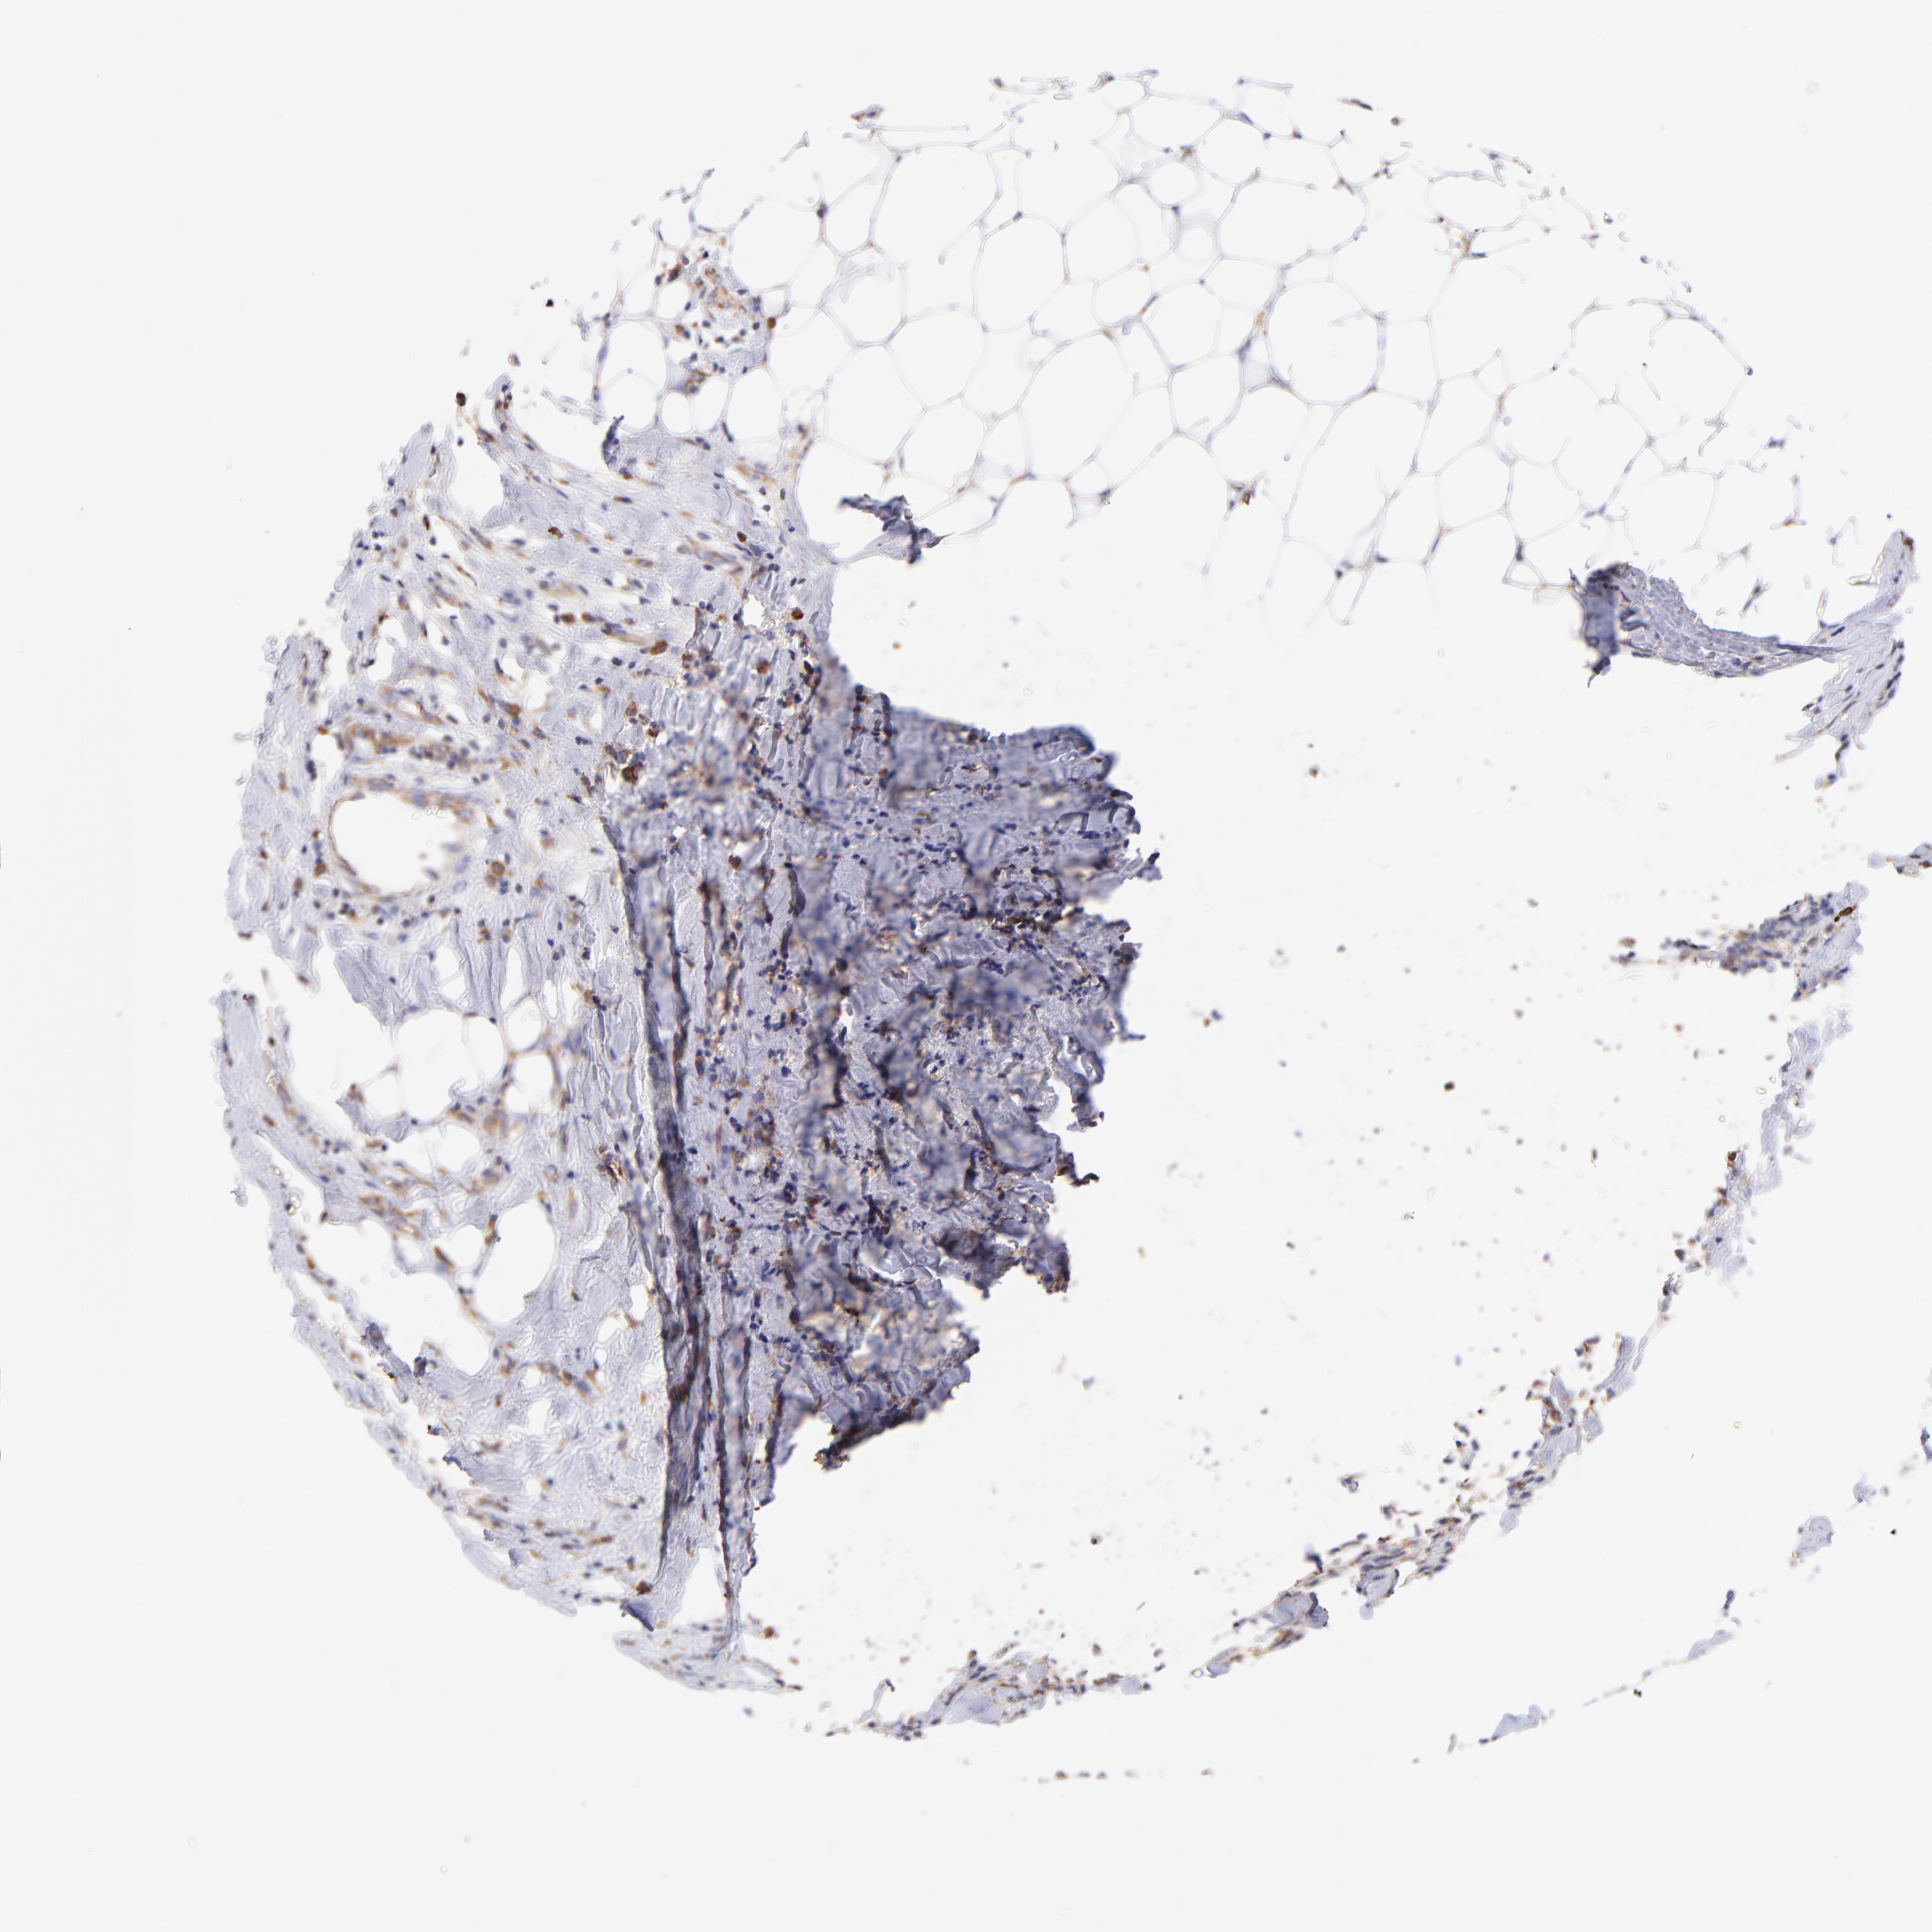

CANCER BREAST CANCER Show tissue menu

BRCA TCGA BRCA VALIDATION PROTEIN EXPRESSION

Breast cancer

Human cancer

Breast invasive carcinoma